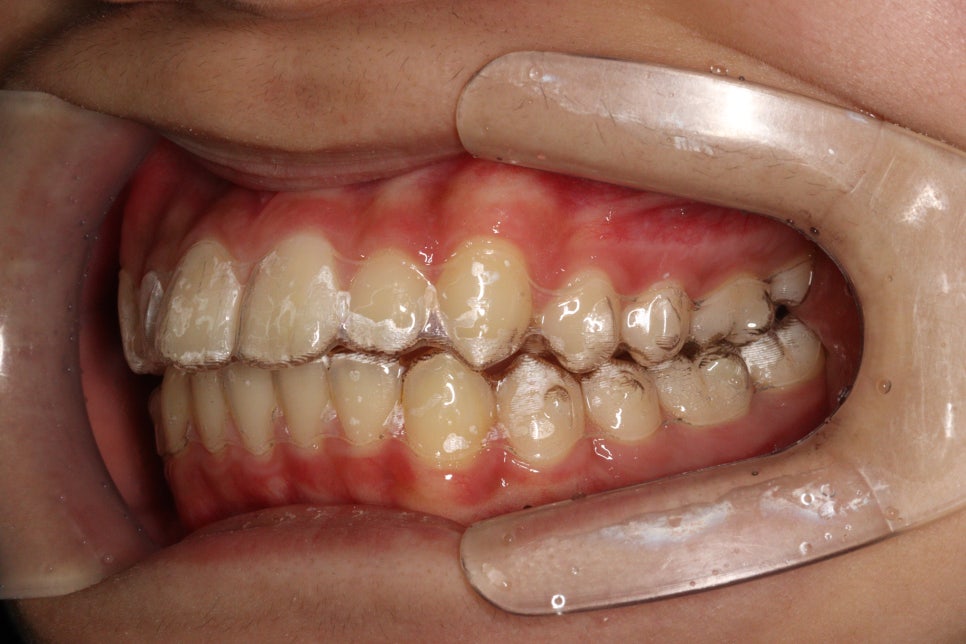

치료 전과 후 입니다.

앞니가 후방이동 한것이 확인됩니다.

우리는 부분교정을 한것이 아니라 간단한 전체교정을 한것입니다.

치아가 들어가보입니다.

앞니만 철사를 붙여서는 얻기 어려운 결과라고 생각합니다.

치료기간 2023.6.20.~2023.12.23.

치료기간 약 4개월